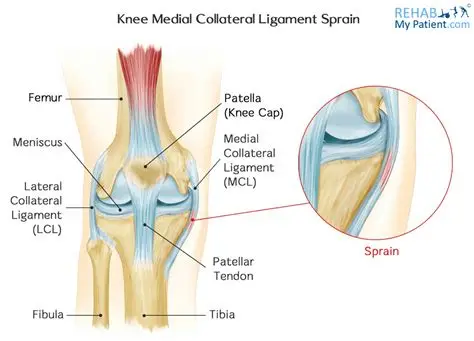

Medial Collateral Ligament Injury

Lateral Collateral Ligament Injury

Posterior Cruciate Ligament Injury